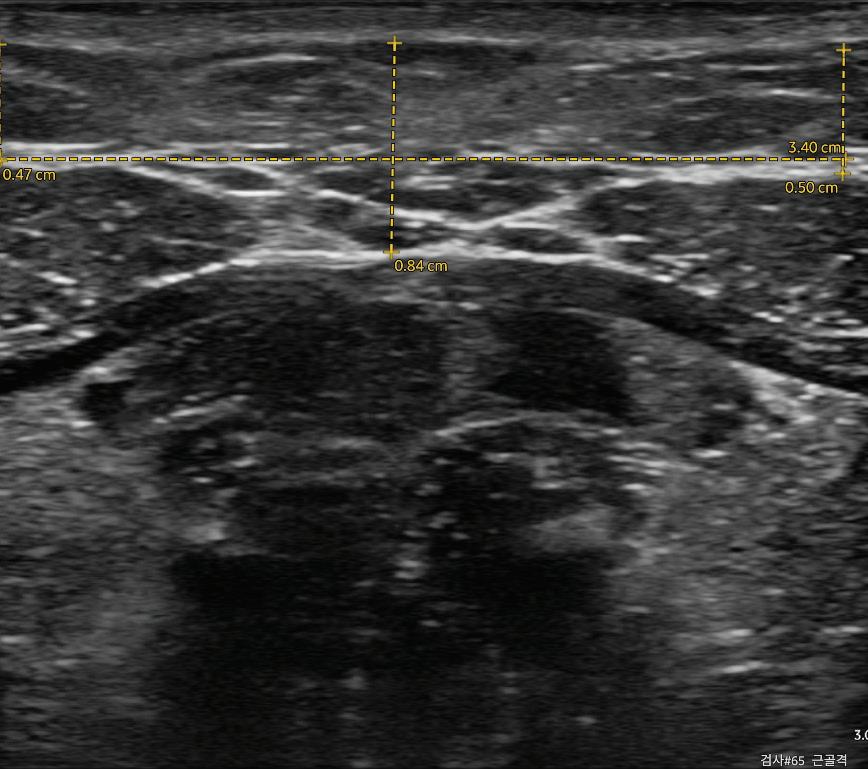

The treatment area was defined as the 'submental triangle,' bordered superiorly by the mandibular line, inferiorly by the hyoid bone, and overlying the mylohyoid muscle. Ultrasound imaging was performed using the Vscan Air™ system to guide injection depth and assess fat layer thickness.

Standardised imaging was conducted along the midline using reference points. For consistent ultrasound imaging, a horizontal reference length of 3.40 cm was defined at the level of the platysma muscle, based on internal calibration, and the anterior belly of the digastric muscle was used bilaterally to ensure consistent positioning. Preplatysmal and subplatysmal fat thicknesses were measured before and after treatment.

Figure 2

Submental fat thickness before and after Bellacholine treatment

Figure 3 Patient 1— photographic and ultrasound imaging. Submental fat thickness (the point where the depth is the longest)(A) baseline (before treatment) measurement: 11.9mm; (B) post-treatment (after 3 Sessions) measurements: 9.8mm

Figure 4 Patient 2 photographic and ultrasound imaging. Submental fat thickness (the point where the depth is the longest)(A) baseline (before treatment) measurement: 12.3 mm; (B) post-treatment (after 3 Sessions) measurements: 8.4mm